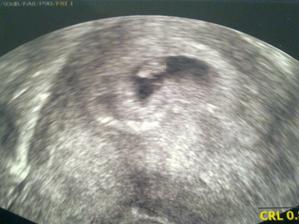

Tak to vše začalo.....